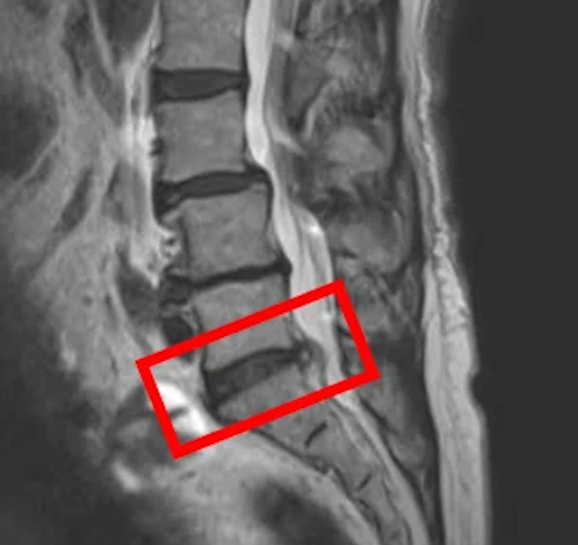

По данным МРТ и результатам осмотра пациента выявлена межпозвоночная грыжа диска L5/S1, дегенерация межпозвоночного диска L2/L3, а также спондилолистез позвонка L4.

Основная причина болей в пояснице – межпозвоночная грыжа диска L5/S1.